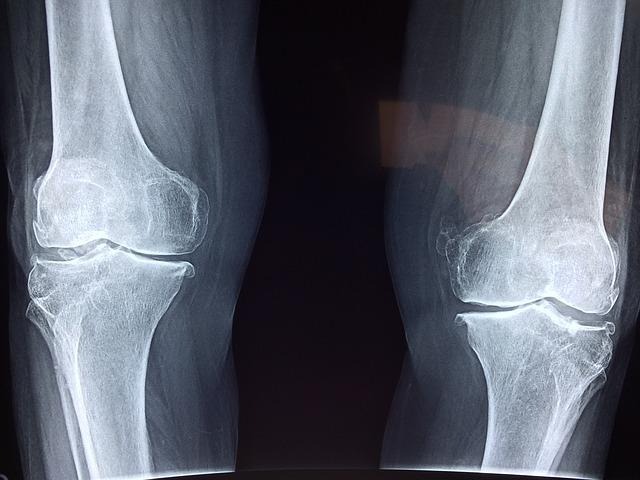

事故当日のうちに整形外科を受診し、診断を受けてください。もし痛みやしびれといった症状が出ている場合は、レントゲンやMRIでの検査をすすめられる場合があります。できるだけこれらの検査を受け、事故の影響があるということを医学的に証明できるようにしておきましょう。